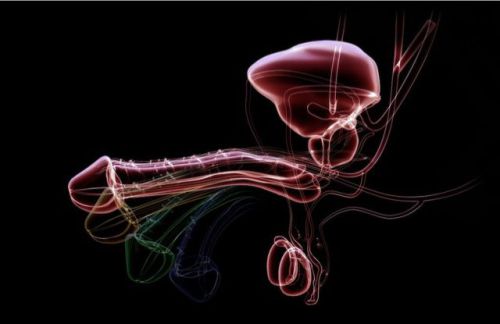

Кавернозография – это рентгенологическое исследование, во время которого через небольшую иглу в кавернозные тела пениса вводят рентген-контрастное вещество. С помощью этого метода доктор оценивает состояние кровеносных сосудов полового члена.

Исследование применяют в сложных случаях. Оно позволяет отличить венозную окклюзию и недостаточность артериального притока, а также определить место сброса венозной крови в артериальное русло пениса.

Пещеристое (кавернозное) тело — это структурная часть полового члена. Пещеристые тела (правое и левое) имеют цилиндрическую форму и расположены внутри полового члена. К вентральной поверхности пещеристых тел, параллельно им, подлежит губчатое (спонгиозное) тело полового члена.

Основу полового члена составляют три кавернозных тела. Два из них, начинающиеся от бугров седалищной кости, соединяясь, образуют тело полового члена, третье — пещеристое тело уретры, окружающее мочеполовой канал и плавно переходящее в губчатое тело головки.